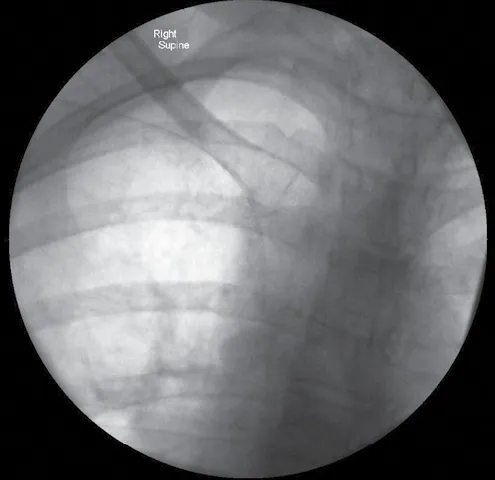

The PICC line is of a similar design to a midline. It is inserted in the same way, but because of its extra length, the tip is placed in the central venous system, i.e., in the super vena cava/cavo-atrial junction. It is usually inserted under x-ray or electrocardiogram (ECG) guidance. It is recommended for use in cases when medium-/long-term central access is required, e.g., for chemotherapy, total parenteral nutrition, etc. PICC lines can last up to 12 months or more if they are well cared for (Figures 1.5 and 1.6).

Figure 1.6 Right-sided PICC x-ray confirmation with the tip approaching the cavo-atrial junction.